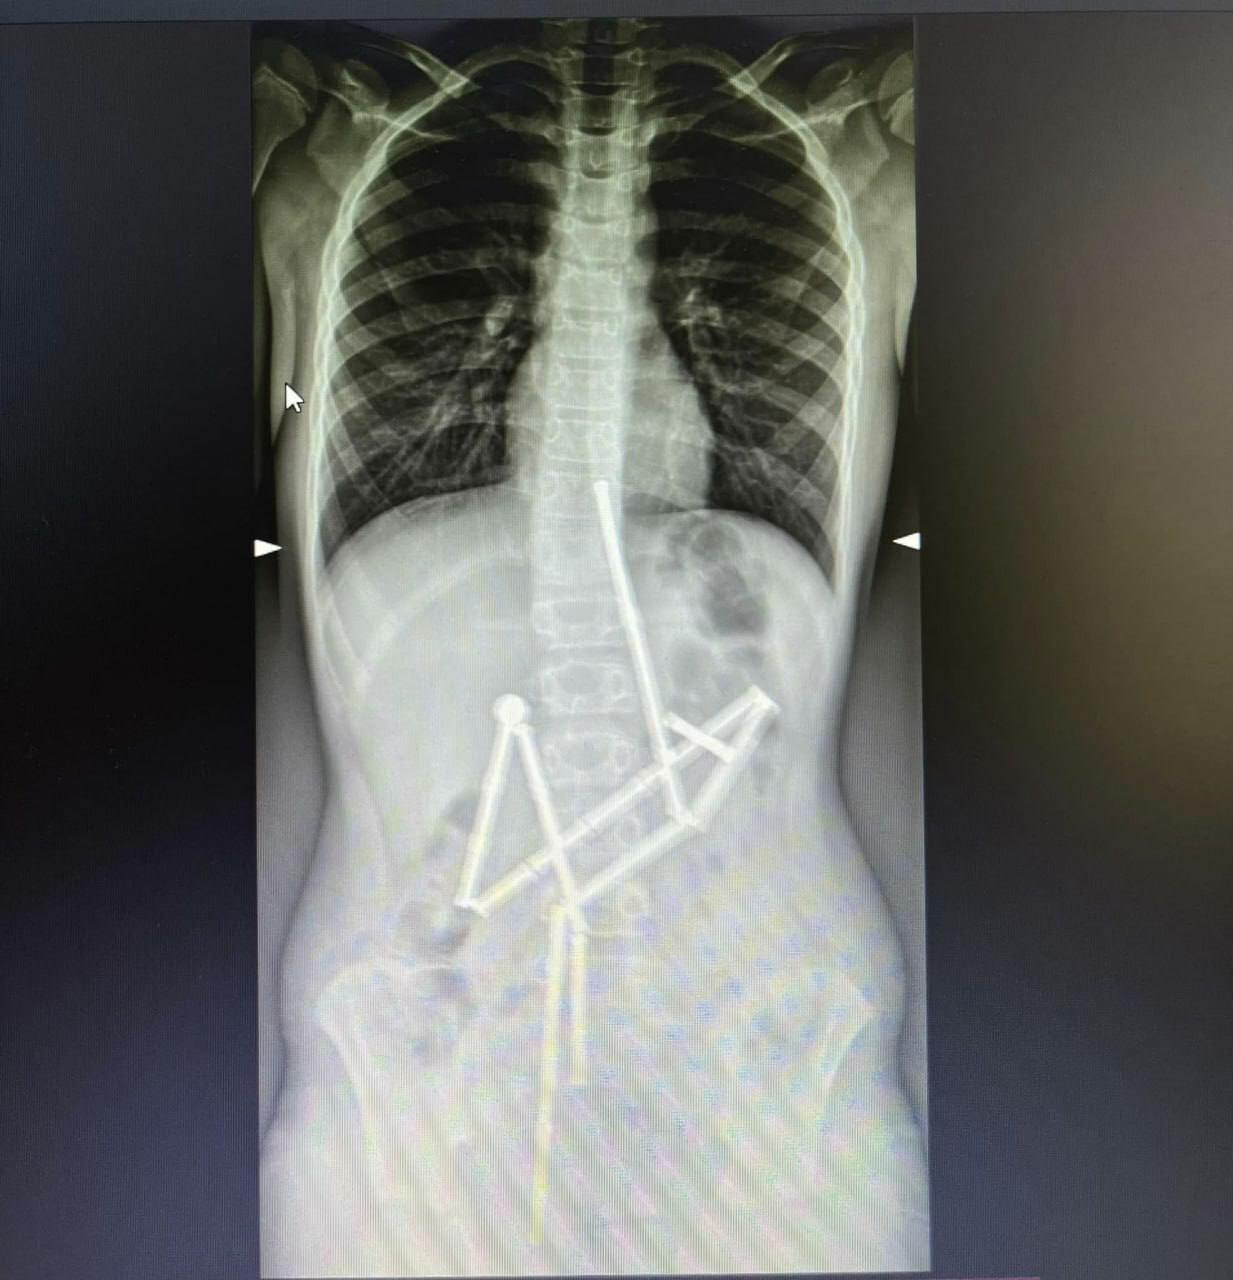

A child swallowed 20 magnets: Okhmatdyt doctors saved her life / Photo: The National Children's Specialized Hospital "Okhmatdyt"

The National Children's Specialized Hospital "Okhmatdyt" saved the life of a child who swallowed 20 magnets.